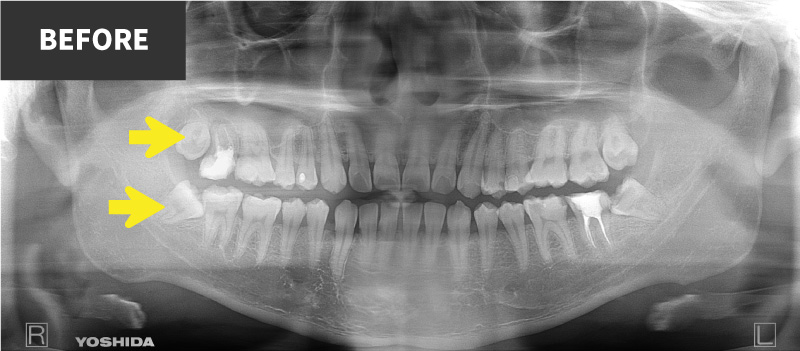

一般歯科診療では敬遠されがちな、重要神経管(下歯槽神経管:下顎の神経と動脈・静脈が入っている管)に接する親知らず

抜く方向や角度を十分にシミュレーションして安全抜歯を心がけている。

上の親知らずには、歯並びと逸脱した方向に生えてしまうものが多くあります。

これらは、咬み合わせに悪影響を及ぼすだけでなく、周囲の歯の虫歯や歯周病の原因となってしまうことがあります。

これらを安全に抜歯することも口腔外科の仕事です。